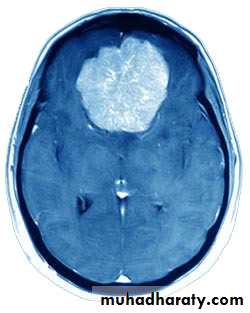

MeningiomaPre contrast CT

Neurosurgery

MeningiomaPost contrast CT

Meningiomas

• These account for 15% of intracranial neoplasms, and are the most common benign neoplasm.

• They occur more frequently in women than in men, and their incidence peaks in middle age.

• The tumour arises from meningothelial cells of the arachnoid villi.

• They classically arise from a broad base along the dura.

• They may invade bone.

• They derive their blood supply from the external carotid circulation.

• Malignant meningiomas are relatively rare.

• The symptoms and signs are related to those of intracranial mass lesions or seizures.

• CT scan accurately diagnoses the lesions.

• Complete surgical removal usually results in cure.